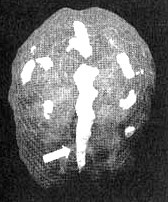

Иллюстрация к книге — Измените свой мозг - изменится и жизнь! [i_057.jpg]

Трехмерное изображение — активный мозг, вид сверху

Иллюстрация к книге — Измените свой мозг - изменится и жизнь! [i_058.jpg]

Трехмерное изображение — активный мозг, вид спереди